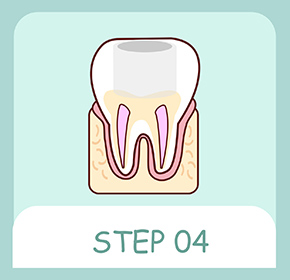

被せ物が安定するように歯を削った部分を埋め、歯の欠損が大きい場合には歯の土台(コア)を造成します。